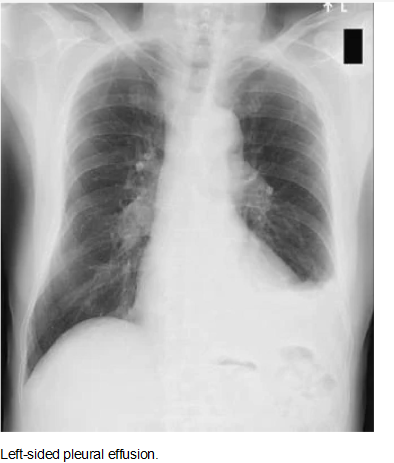

Chest Radiography

Effusions of more than

175 mL are usually apparent as blunting of the

costophrenic angle on upright posteroanterior

chest radiographs. On supine chest radiographs,

which are commonly used in the intensive care

setting, moderate to large pleural effusions may

appear as a homogeneous increase in density

spread over the lower lung fields. Apparent

elevation of the hemidiaphragm, lateral

displacement of the dome of the diaphragm, or

increased distance between the apparent left

hemidiaphragm and the gastric air bubble

suggests subpulmonic effusions.

Bilateral

pleural effusions with loss of bilateral

costophrenic sulci (meniscus sign).

Anteroposterior, upright chest radiograph.

Lateral decubitus films more reliably detect

smaller pleural effusions. Layering of an

effusion on lateral decubitus films defines a

freely flowing effusion and, if the layering

fluid is 1 cm thick, indicates an effusion of

greater than 200 mL that is amenable to

thoracentesis. Failure of an effusion to layer

on lateral decubitus films indicates the

presence of loculated pleural fluid or some

other etiology causing the increased pleural

density. Note that decubitus films are almost

never performed in those institutions with

bedside ultrasonography.

Left lateral

decubitus film displaying freely layering

left-sided pleural effusion.